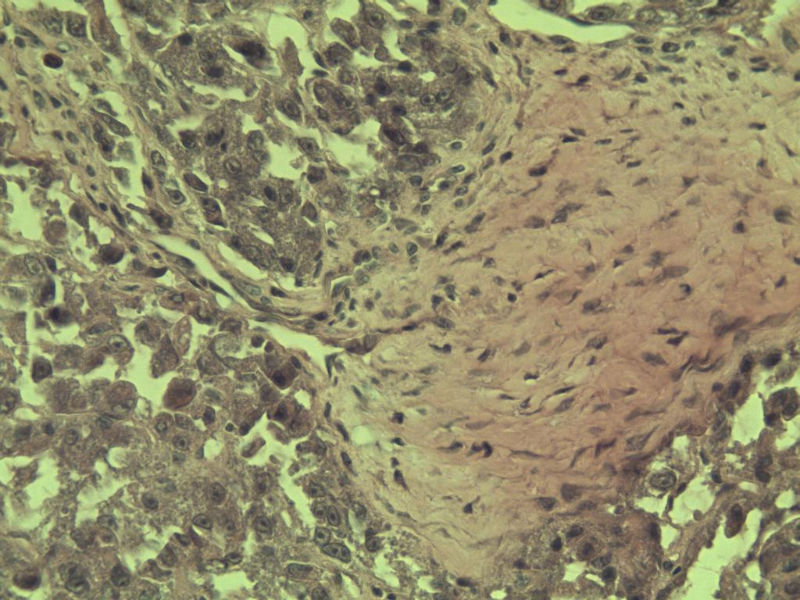

女 70岁 右颈部 头皮 多发皮下结节      取颈部部分结节送检 灰白小组织 1 块,直径 0.4 cm。 请问这个是什么?

肿瘤细胞大,上皮样,核空泡状,核仁明显,胞质嗜酸性或透明。

考虑:恶性黑色素瘤?

近心型上皮样肉瘤?

软组织透明细胞肉瘤?

上皮样多形性脂肪肉瘤?

等免疫组化标记!

此片染色欠佳,取材或切面也有问题,加大了诊断的难度,恶黑确实需要考虑,但其他一些转移癌也需要排除,比如肺癌之类的,还是期待免疫组化!